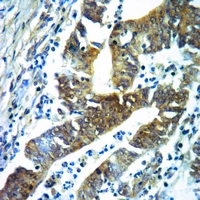

Immunohistochemical analysis of Acetylcholinesterase staining in human brain formalin fixed paraffin embedded tissue section. The section was pre-treated using heat mediated antigen retrieval with sodium citrate buffer (pH 6.0). The section was then incubated with the antibody at room temperature and detected using an HRP conjugated compact polymer system. DAB was used as the chromogen. The section was then counterstained with haematoxylin and mounted with DPX. -